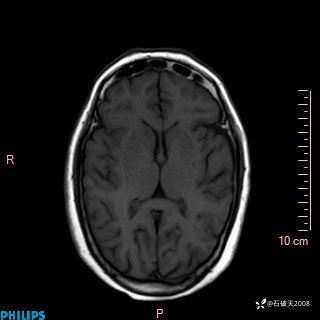

2020.11.14MR

FLAIR